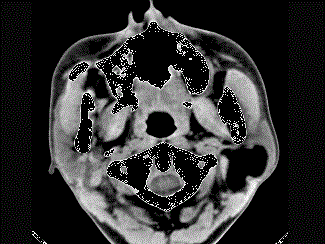

问题 女性50岁,左侧面部肿胀,CT检查如图,应考虑为 ( )

选项 A、左侧腮腺错构瘤 B、左侧腮腺炎 C、左侧腮腺囊肿 D、左侧腮腺脂肪瘤 E、左侧腮腺囊腺瘤

答案 D